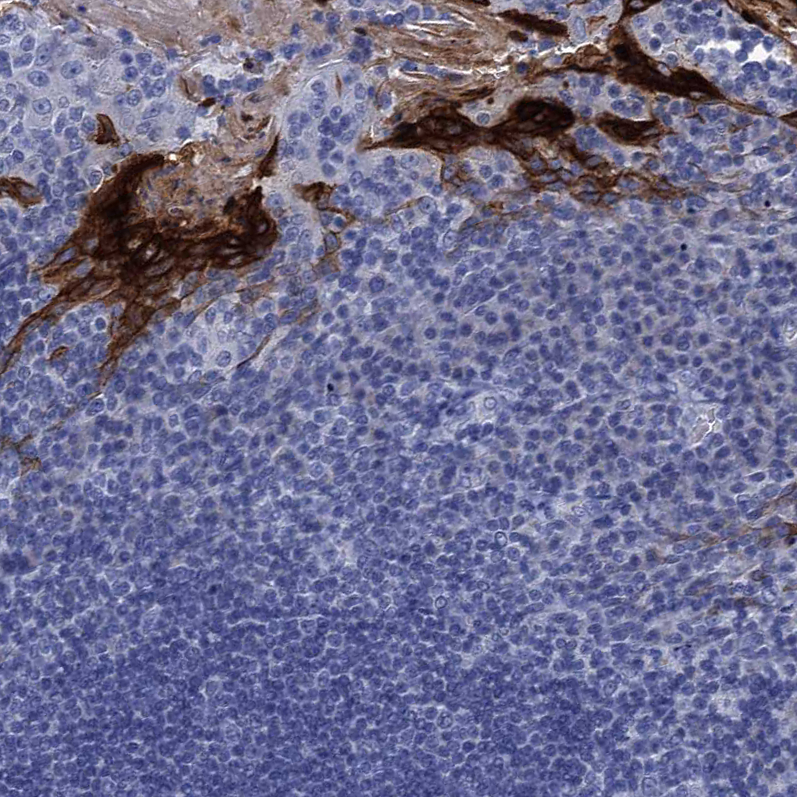

Immunohistochemistry analysis in human esophagus and liver tissues using HPA040154 antibody. Corresponding SCEL RNA-seq data are presented for the same tissues.